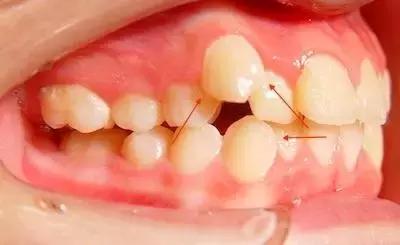

2/ 牙齿因为错位或扭转造成了牙齿之间的间隙。